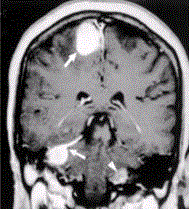

问题 患者男,20岁,头痛、步态不稳。MRI显示如下图。 下图影像学表现可诊断为

选项 A.神经纤维瘤病Ⅱ型 B.神经纤维瘤病Ⅰ型 C.多发脑膜瘤 D.多发神经鞘瘤 E.多发脑转移瘤

答案 A